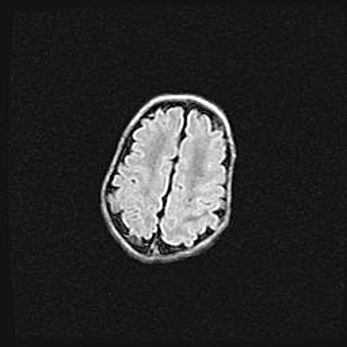

Открытая гидроцефалия.

Возраст: 9 месяцев 12 дней

Вес: 6800 г

Пол: мужской

Окружность головы: 41,5 см

Срок гестации: 28 недель

Гидроцефалия головного мозга у новорожденных имеет характерный признак: опережающий рост окружности головы приводит к визуально хорошо определяемой гидроцефальной форме сильно увеличенного в объёме черепа. Детские неврологи определяют следующие симптомы гидроцефалии у грудничков: выбухающий напряжённый родничок, частое запрокидывание головы, смещение глазных яблок к низу.